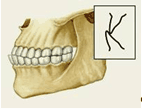

Существует множество классификаций аномалий П., однако общепринятой является международная классификация, предложенная в 1899 г. Энглом (Е.Н. Angle). В ее основе лежит соотношение первых моляров, что, по мнению Энгла, служит ключом окклюзии. В соответствии с классификацией к первому классу (рис. 6, а) относятся все аномалии, при которых первые моляры находятся в правильном соотношении (мезиально-шеечный бугор первого моляра верхней челюсти располагается в межбугорковой фиссуре первого моляра нижней челюсти), а все аномалии П. обусловлены изменениями зубов или челюстей спереди от первых моляров, например при скученности резцов, их протрузии (наклоне в сторону преддверия рта) или ретрузии (наклоне в сторону полости рта).

Во второй класс включены аномалии, при которых нарушено смыкание первых моляров и фронтальной группы зубов. Межбугорковая фиссура первого моляра нижней челюсти располагается позади мезиально-щечного бугра первого моляра верхней челюсти, т.е. нарушено смыкание зубов в сагиттальной плоскости (переднезаднем направлении). Подобные нарушения (так называемый дистальный прикус) могут быть обусловлены чрезмерным ростом верхней челюсти (прогнатией) или (реже) недоразвитием нижней челюсти (микрогенией). В зависимости от положения и смыкания фронтальной группы зубов во втором классе выделяют два подкласса: первый характеризуется протрузией резцов (рис. 6, б), второй — их ретрузией (рис. 6, в).

Третий класс (рис. 6, г) включает аномалии П., при которых межбугорковая фиссура первого моляра нижней челюсти располагается впереди мезиально-щечного бугра одноименного моляра верхней челюсти (мезиальный П., прогения, прогенический П., антериальный П.).

Рис. 6. Схематическое изображение челюстей при сагиттальных аномалиях прикуса, по классификации Энгла: а — аномалии первого класса; б — аномалии второго класса, первого подкласса; в — аномалии второго класса, второго подкласса; г — аномалии третьего класса; вертикальными линиями указано соотношение верхнего и нижнего первых моляров.